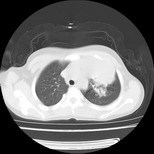

标题: PED3145:女,12岁,前期发热,咳嗽,无痰,CT右肺上叶实变 [打印本页]

标题: PED3145:女,12岁,前期发热,咳嗽,无痰,CT右肺上叶实变

女,12岁,前期发热,咳嗽,无痰,经头孢抗炎无效。ct右肺上叶实变影.5天后公布病理结果。以下是2010-2-13ct片

定位肺外,年龄小,还是先考虑畸胎瘤,左上肺膨胀不全并炎症。

鉴别:内胚窦瘤恶性程度高,有胸水;淋巴瘤、胸腺瘤、sftp等年龄大;异物上叶少见,无肺气肿及纵膈偏移不支持;炎症定位不考虑肺内所以排除。